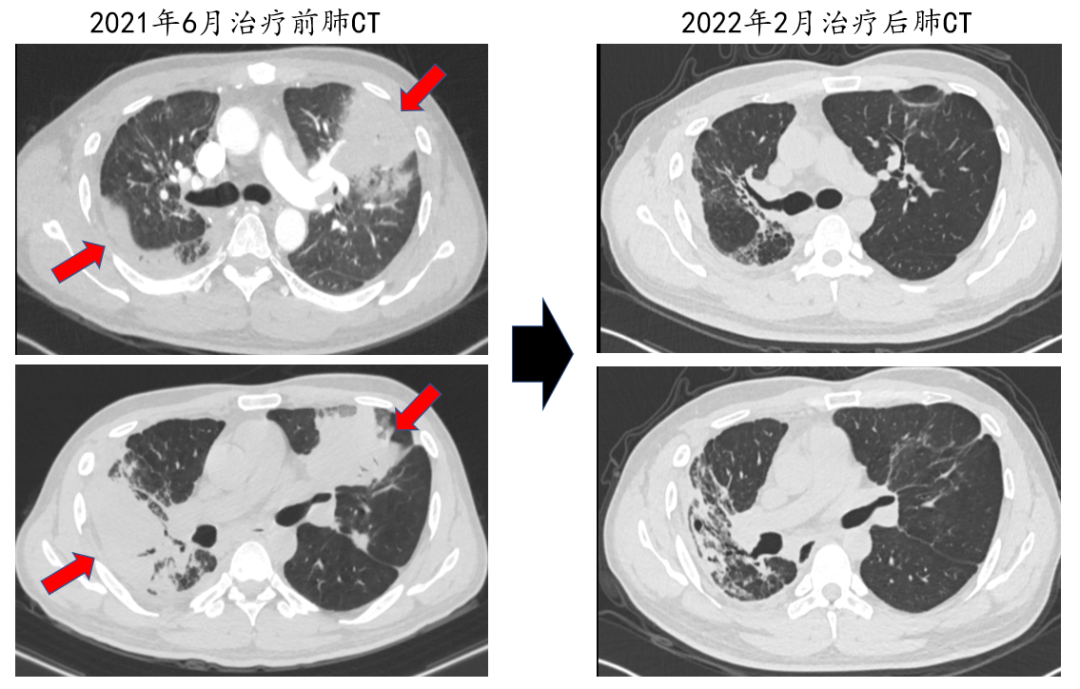

▲治疗半年后复查的肺CT和治疗前的肺CT比较:两肺炎症病变(红色箭头)明显吸收好转。